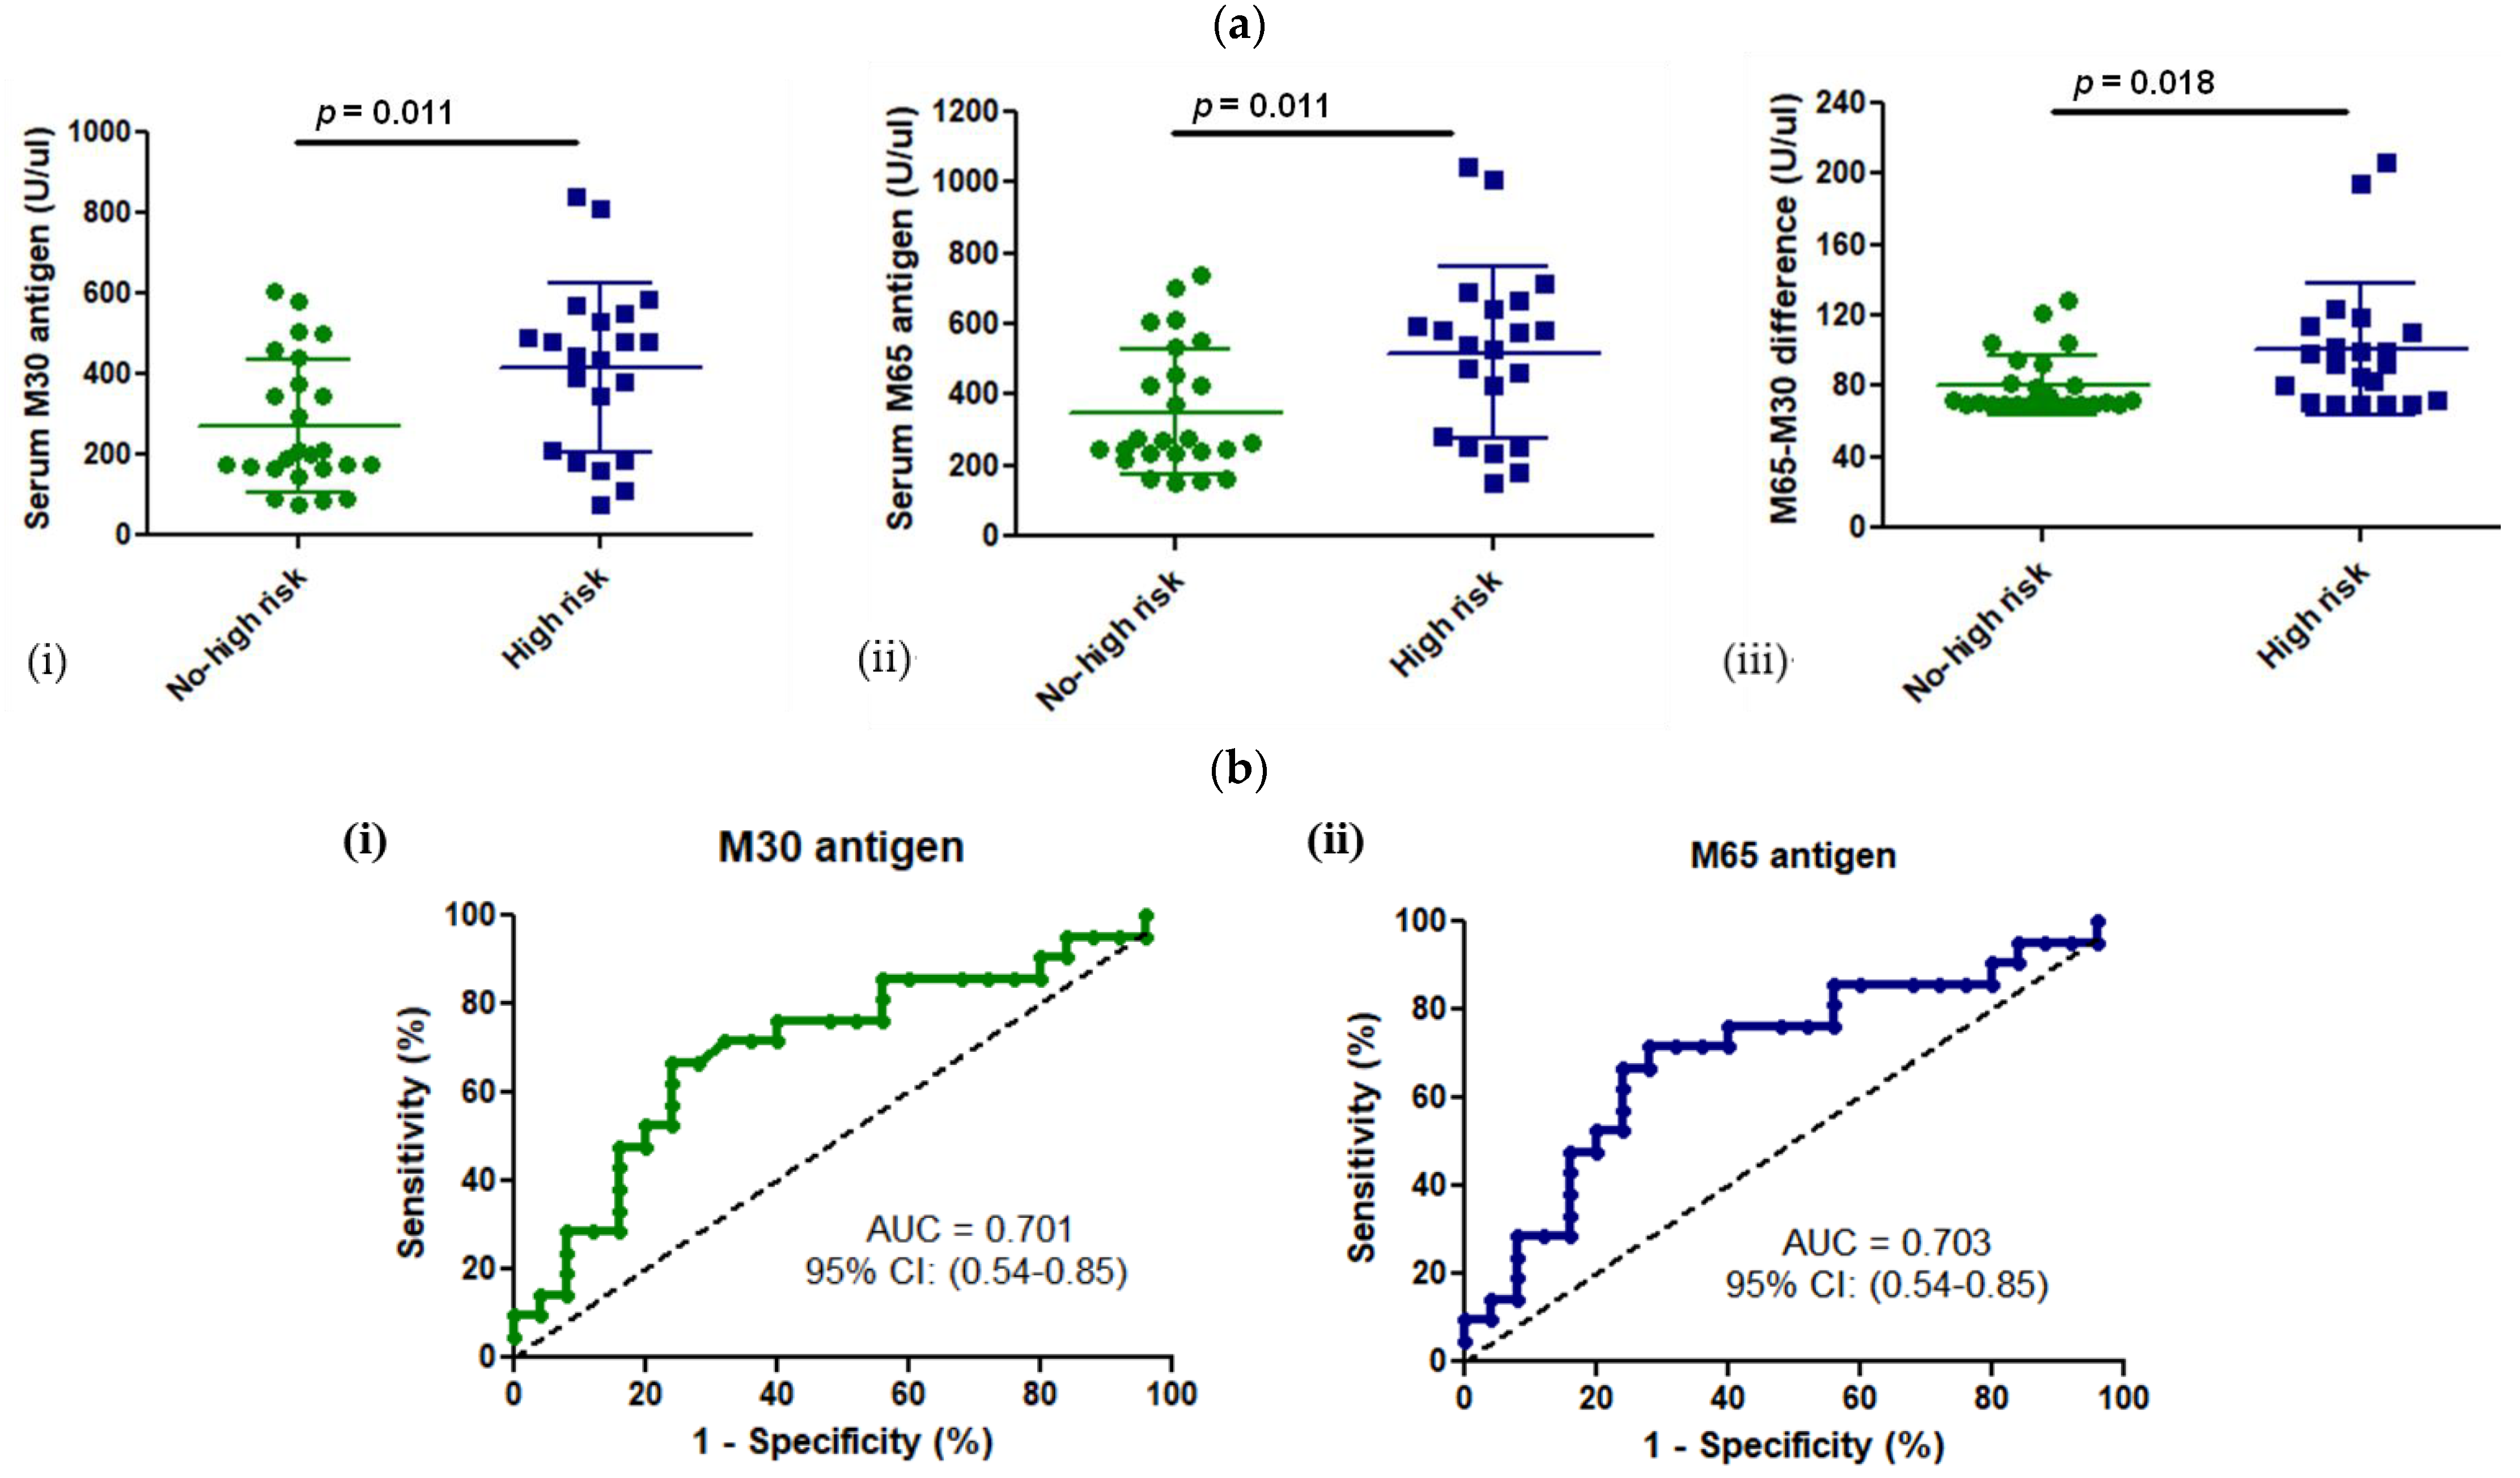

3.3. M30 and M65 Expression in HCM Group with or without High Risk for SCD